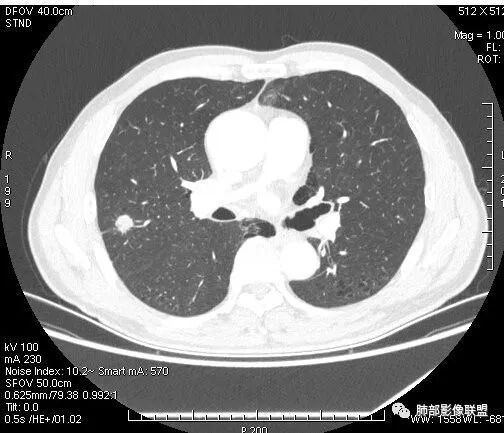

患者右上肺占位,内部强化不均,有空泡,有血管穿过,血管聚集现象,似有胸膜牵拉,考虑恶性

右肺上叶后段占位病灶,病灶不规则,周围胸膜线性牵拉,病灶部分周围有晕,病灶内见不规则空洞,未见明显引流支气管,长毛刺,多分叶、肿块边缘部分L型,可见血管直接供养。增强见点状坏死、病灶内血管。综上考虑恶性可能性大,鉴别隐球菌。

右肺上叶结节,浅分叶膨隆,边缘可见胸膜牵拉及血管集束,不规则厚壁空洞,不均匀强化,血管进入病灶,边缘毛燥,考虑低分化腺癌,鉴别隐球菌。

来个不一样的,小病灶近心端空洞,分叶,毛刺软,长,收缩力差,强化明显,血管走形自然,无明显卫星灶,先考虑炎性,肉芽肿炎,隐球菌可能性大,不排除肿瘤,需要活检

右肺团块影,深分叶,有毛刺,但毛刺偏软。团块附近有血管走行,穿过。血管增粗,僵直。空洞近心,团块周围似有卫星灶。良,恶性征象都有;按可能性排序:隐球,结核,腺癌。

右肺结节,分叶、长短毛刺,边缘略膨隆,胸膜牵拉,血管进入病灶,收缩力较弱,有血管聚集征,洞壁尚规整,低强化,坏死边缘规整。考虑炎性,隐球,鉴别腺癌。

晨读,右肺上叶结节,边缘膨隆、分叶,部分边缘有平直,可见多发毛刺及胸膜牵拉,牵拉线清秀,收缩力弱,内密度不均,可见片状低密度影及空洞,增强后不均匀强化,血管集束,考虑良性,肉芽肿性结节,鉴别腺癌

晨读:双肺胸膜下多发小气囊,大小不一,右肺结节,内部可见小空洞,洞壁光滑,厚薄不一,偏心性生长,近段血管束增粗,有分叶,毛刺(软),有晕征,平扫密度尚可,增强后不均匀强化,可见低密度坏死,及部分血管穿行,体检发现,考虑恶性:腺癌,鉴别炎性结节

晨读:右肺中叶结节,浅分叶,边缘膨隆,胸膜牵拉,不规则偏心厚壁小空洞,空洞壁可见低密度坏死,不均匀强化,血管进入病灶,边缘毛燥,考虑鳞癌。鉴别肉芽肿

右肺上叶结节,边界清,有分叶,厚壁空洞,强化后见坏死区,血管进入病灶,考虑结核。

右上叶结节,轻分叶,结节有长短不一毛刺,结节周围GGO边界清,有血管集束征,肺窗结节周围似可见卫星灶,可见鬼脸征,良恶性征象都有,但GGO边界清,浸润性腺癌耍考虑,临床症状轻微,体捡发现,似可见卫星灶和鬼脸征,炎性肉芽肿TB或隐球菌要鉴别。

影像学改变:

1.右肺上叶后段类圆形结节影,密度不均,有坏死空洞,坏死比较彻底,内外壁都较清楚。

2.病灶有浅切迹,没有深分叶,毛刺大多细长且柔软。

3.可见棘状突起及胸膜牵拉,但未见胸膜凹陷。

什么意思?结节影有牵拉的动作,但似乎“出工不出力”,收缩力羸弱!

4.病灶轻到中度强化。病灶内血管走行较完好,病灶旁血管局部显示粗大。

5.支气管关系不确定。

6.灶周见小结节影(卫星灶),边界不甚清晰。